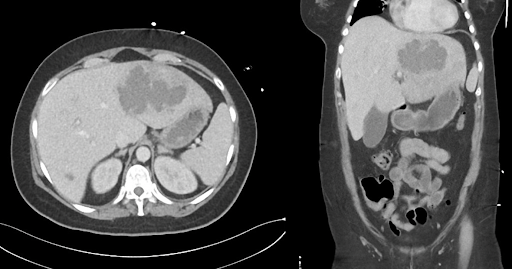

CT abdomen with contrast medium:

Abdominal CT scan with contrast medium

Amoebic liver abscess caused by Entamoeba histolytica, presumably acquired during NGO work in Bangladesh.

Overall, the combination of epidemiological history, clinical presentation, imaging and positive serology makes the diagnosis of amoebic liver abscess the most likely.